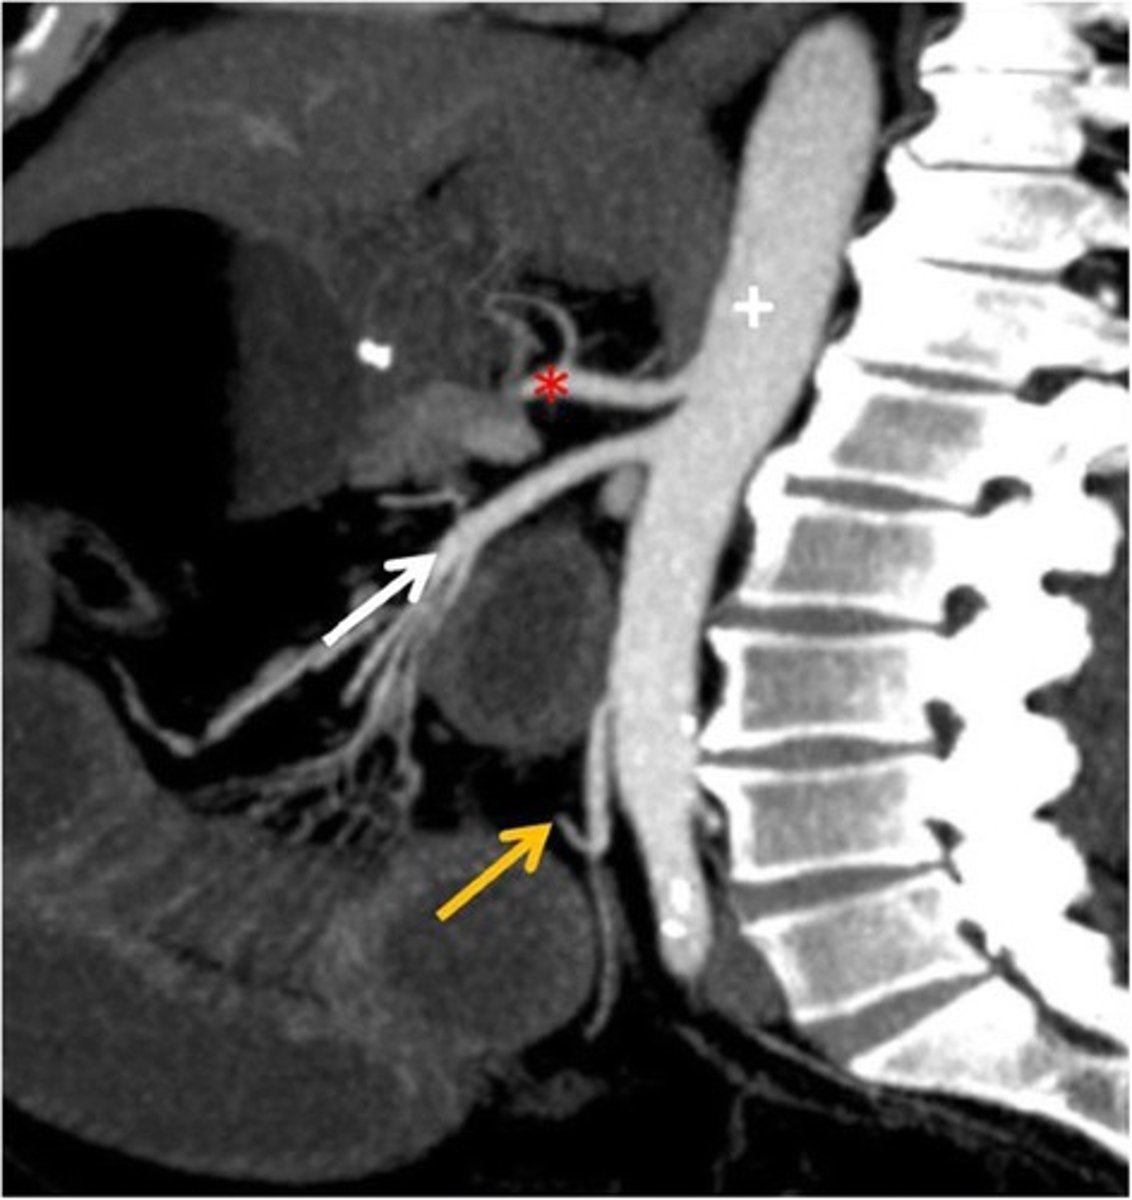

CT Sagittal

What type of image is this

Celiac trunk

What is the red star artery

superior mesenteric artery: midgut

What is the white arrow artery

Inferior mesenteric artery; hindgut

What is the yellow arrow artery